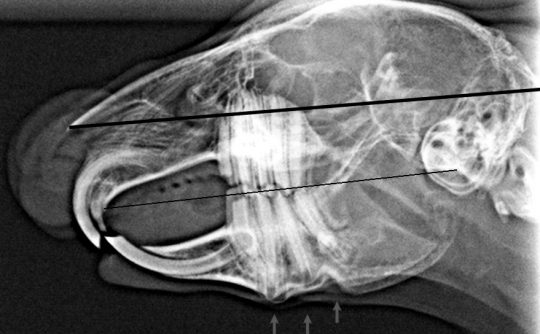

Mandibula angusta bei einem Vorstehhund Tierarzt Dr. Neu

Source: www.dr-peter-neu.de

Viele fehlstellungen deuten sich bereits im milchgebiss an. Zähneputzen beim hund ist sinnvoll und wichtig. Die zahnspange beim hund wird unter narkose eingesetzt.